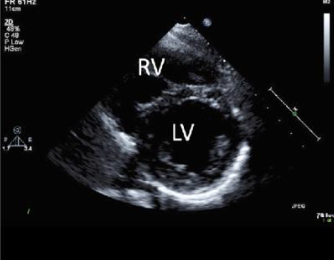

what view is this

parasternal short axis

how is the transducer placed on psax

3 4 5 ics

but rotated 90 of the plax

how should the ventricles look like in psax

lv is round

rv is d